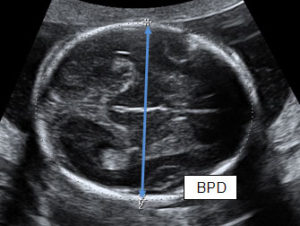

Tính tuổi thai dựa vào đường kính lưỡng đỉnh (BPD: Biparietal Diameter)

Khi Chiều dài đầu mông CRL ≥ 84mm thì việc xác đính tuổi thai không còn chính xác.

Người ta thay thế bằng Đường kính lưỡng đỉnh BPD, áp dụng từ cuối tam cá nguyệt thứ nhất đến 28 tuần tuổi.

Đường kính lưỡng đỉnh là số đo qua siêu âm nơi lớn nhất từ trán ra gáy thai nhi.

Công thức tính tuổi thai theo bảng dưới đây: